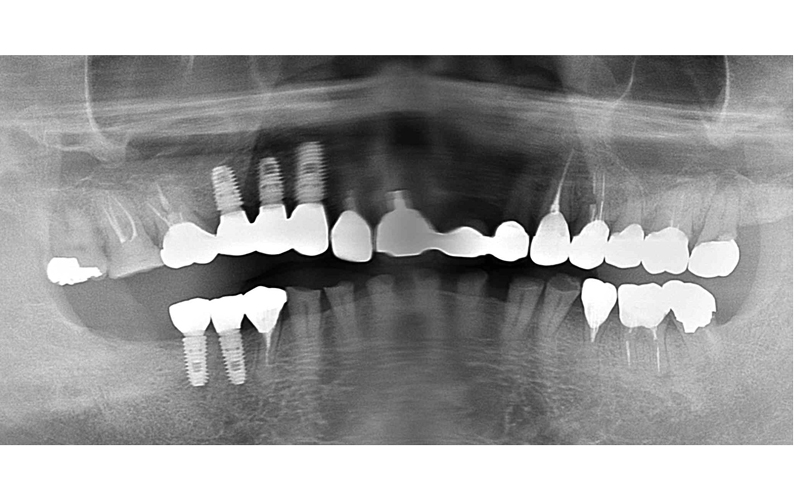

After